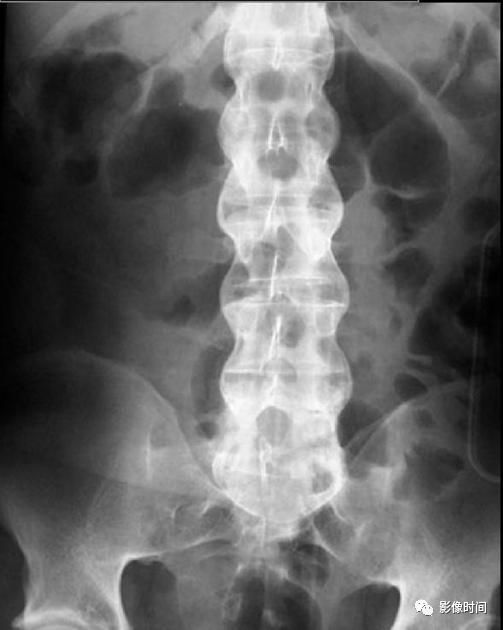

19竹节椎

竹节椎(Bamboo spine)

竹节椎是用于描述强直性脊柱炎的一个放射学特征,由于椎旁韧带广泛骨化,导致椎体融合强直,这种薄而连续的韧带骨化在正位片使得脊柱的轮廓呈现波浪起伏状,宛如具有多个竹节的一根竹竿,故而得名。

典型病例

强直性脊柱炎。腰椎正位片示腰椎韧带、小关节囊广泛骨化,骨性强直,呈典型竹节椎表现。另可见骶髂关节骨性融合。

引用自:https://radiopaedia.org/ articles/ bamboo-spine-ankylosing-spondylitis